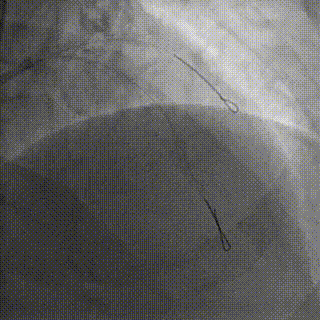

PCI过程

7F XB3.5,Cosair,Runthrough中间支保护,Pilot200正向进入D1,Pilot200 无法通过病变,交换Judo导丝

更换Judo3顺利到达LAD远端,Cosair跟进交换Runthrough

Ballon 2.0*15mm Dilatation & IVUS check

LAD-LM DES 2.75*20mm,2.75*18mm,3.0*30mm

Ballon 2.0*15mm Dilatation for D1 Ostial

NC Ballon & IVUS check

Final result:TIMI3